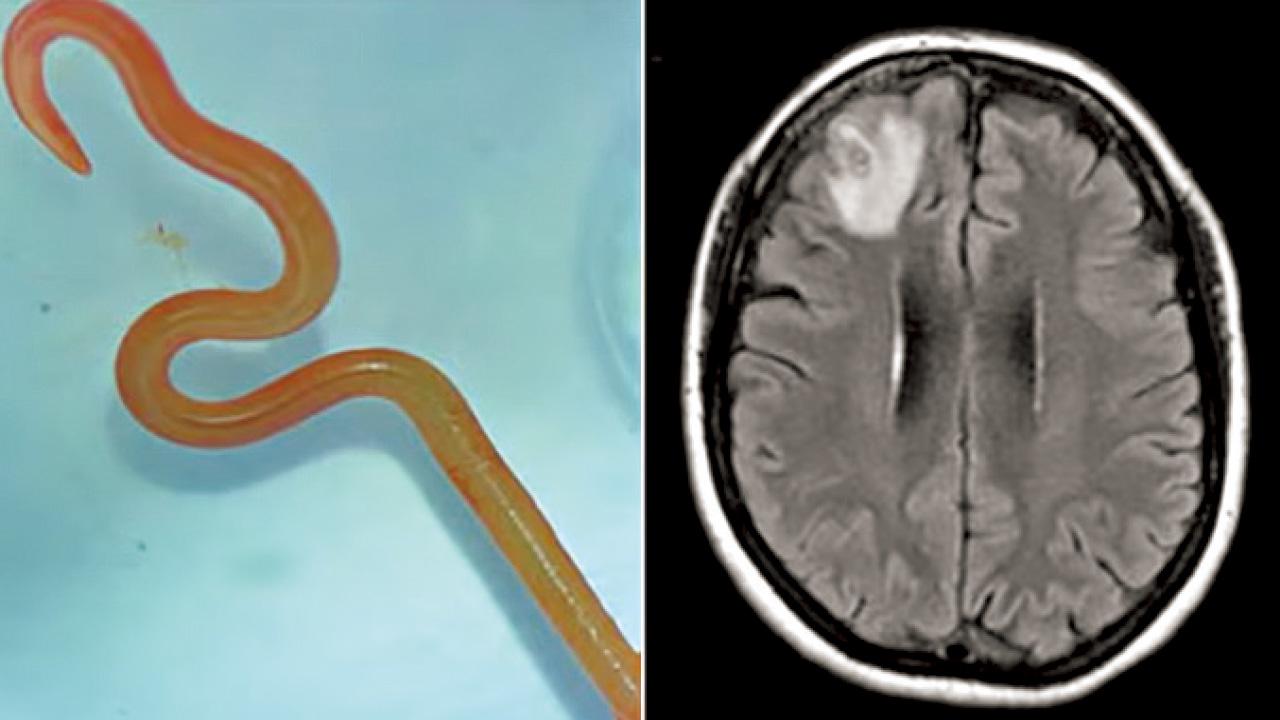

• 源自蟒蛇 全球首例 澳婦腦部取出8厘米活寄生蟲

源自蟒蛇 全球首例 澳婦腦部取出8厘米活寄生蟲